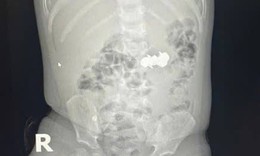

Cứu người bị áp xe ổ bụng hiếm gặp do mắc xương cá

Tin nóng y tế - 09/10/2025 20:05SKĐS - Chiều 9/10, Bệnh viện Lê Văn Việt (TPHCM) cho hay, các bác sĩ khoa Ngoại Tổng hợp vừa phẫu thuật thành công một ca áp xe ổ bụng do dị vật xương cá có thể nguy hiểm đến tính mạng nếu chậm trễ xử trí.